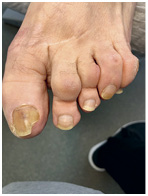

Результат работы за 5 месяцев: подолог использовал крючковые коррекционные системы, а хирург сделал пластику внутреннего бокового валика (из-за хронических воспалений боковой валик стал гипертрофированным и давил на ноготь, от чего клиент испытывал постоянный дискомфорт)